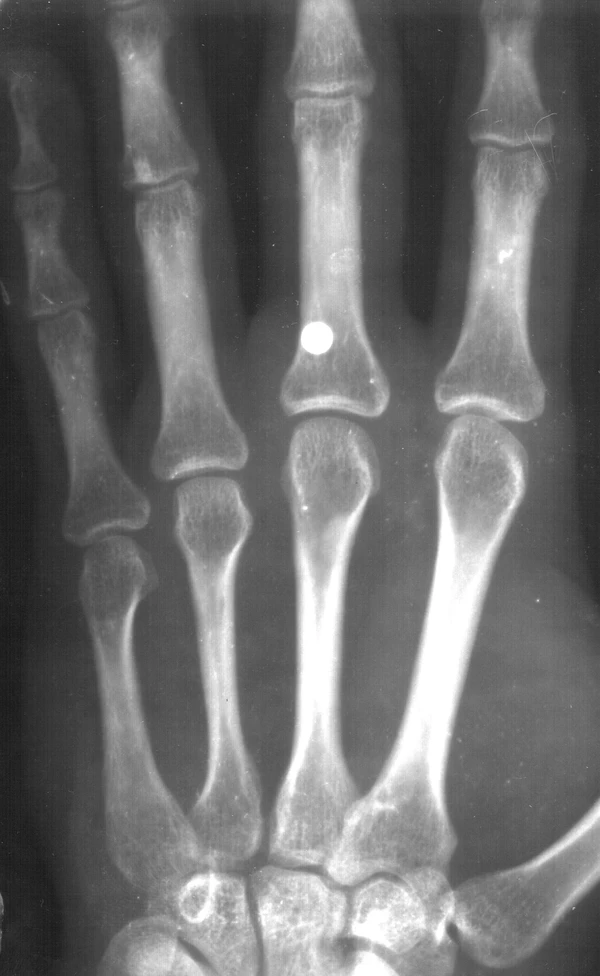

Иноро́дное те́ло (лат. corpus alienum) — с медицинской точки зрения любой чужеродный предмет, попавший внутрь организма. В узком смысле — посторонние предметы различных размеров, попавшие в глаз, ухо, нос, глотку, гортань, в пищевод или трахею (дыхательное горло), заноза.